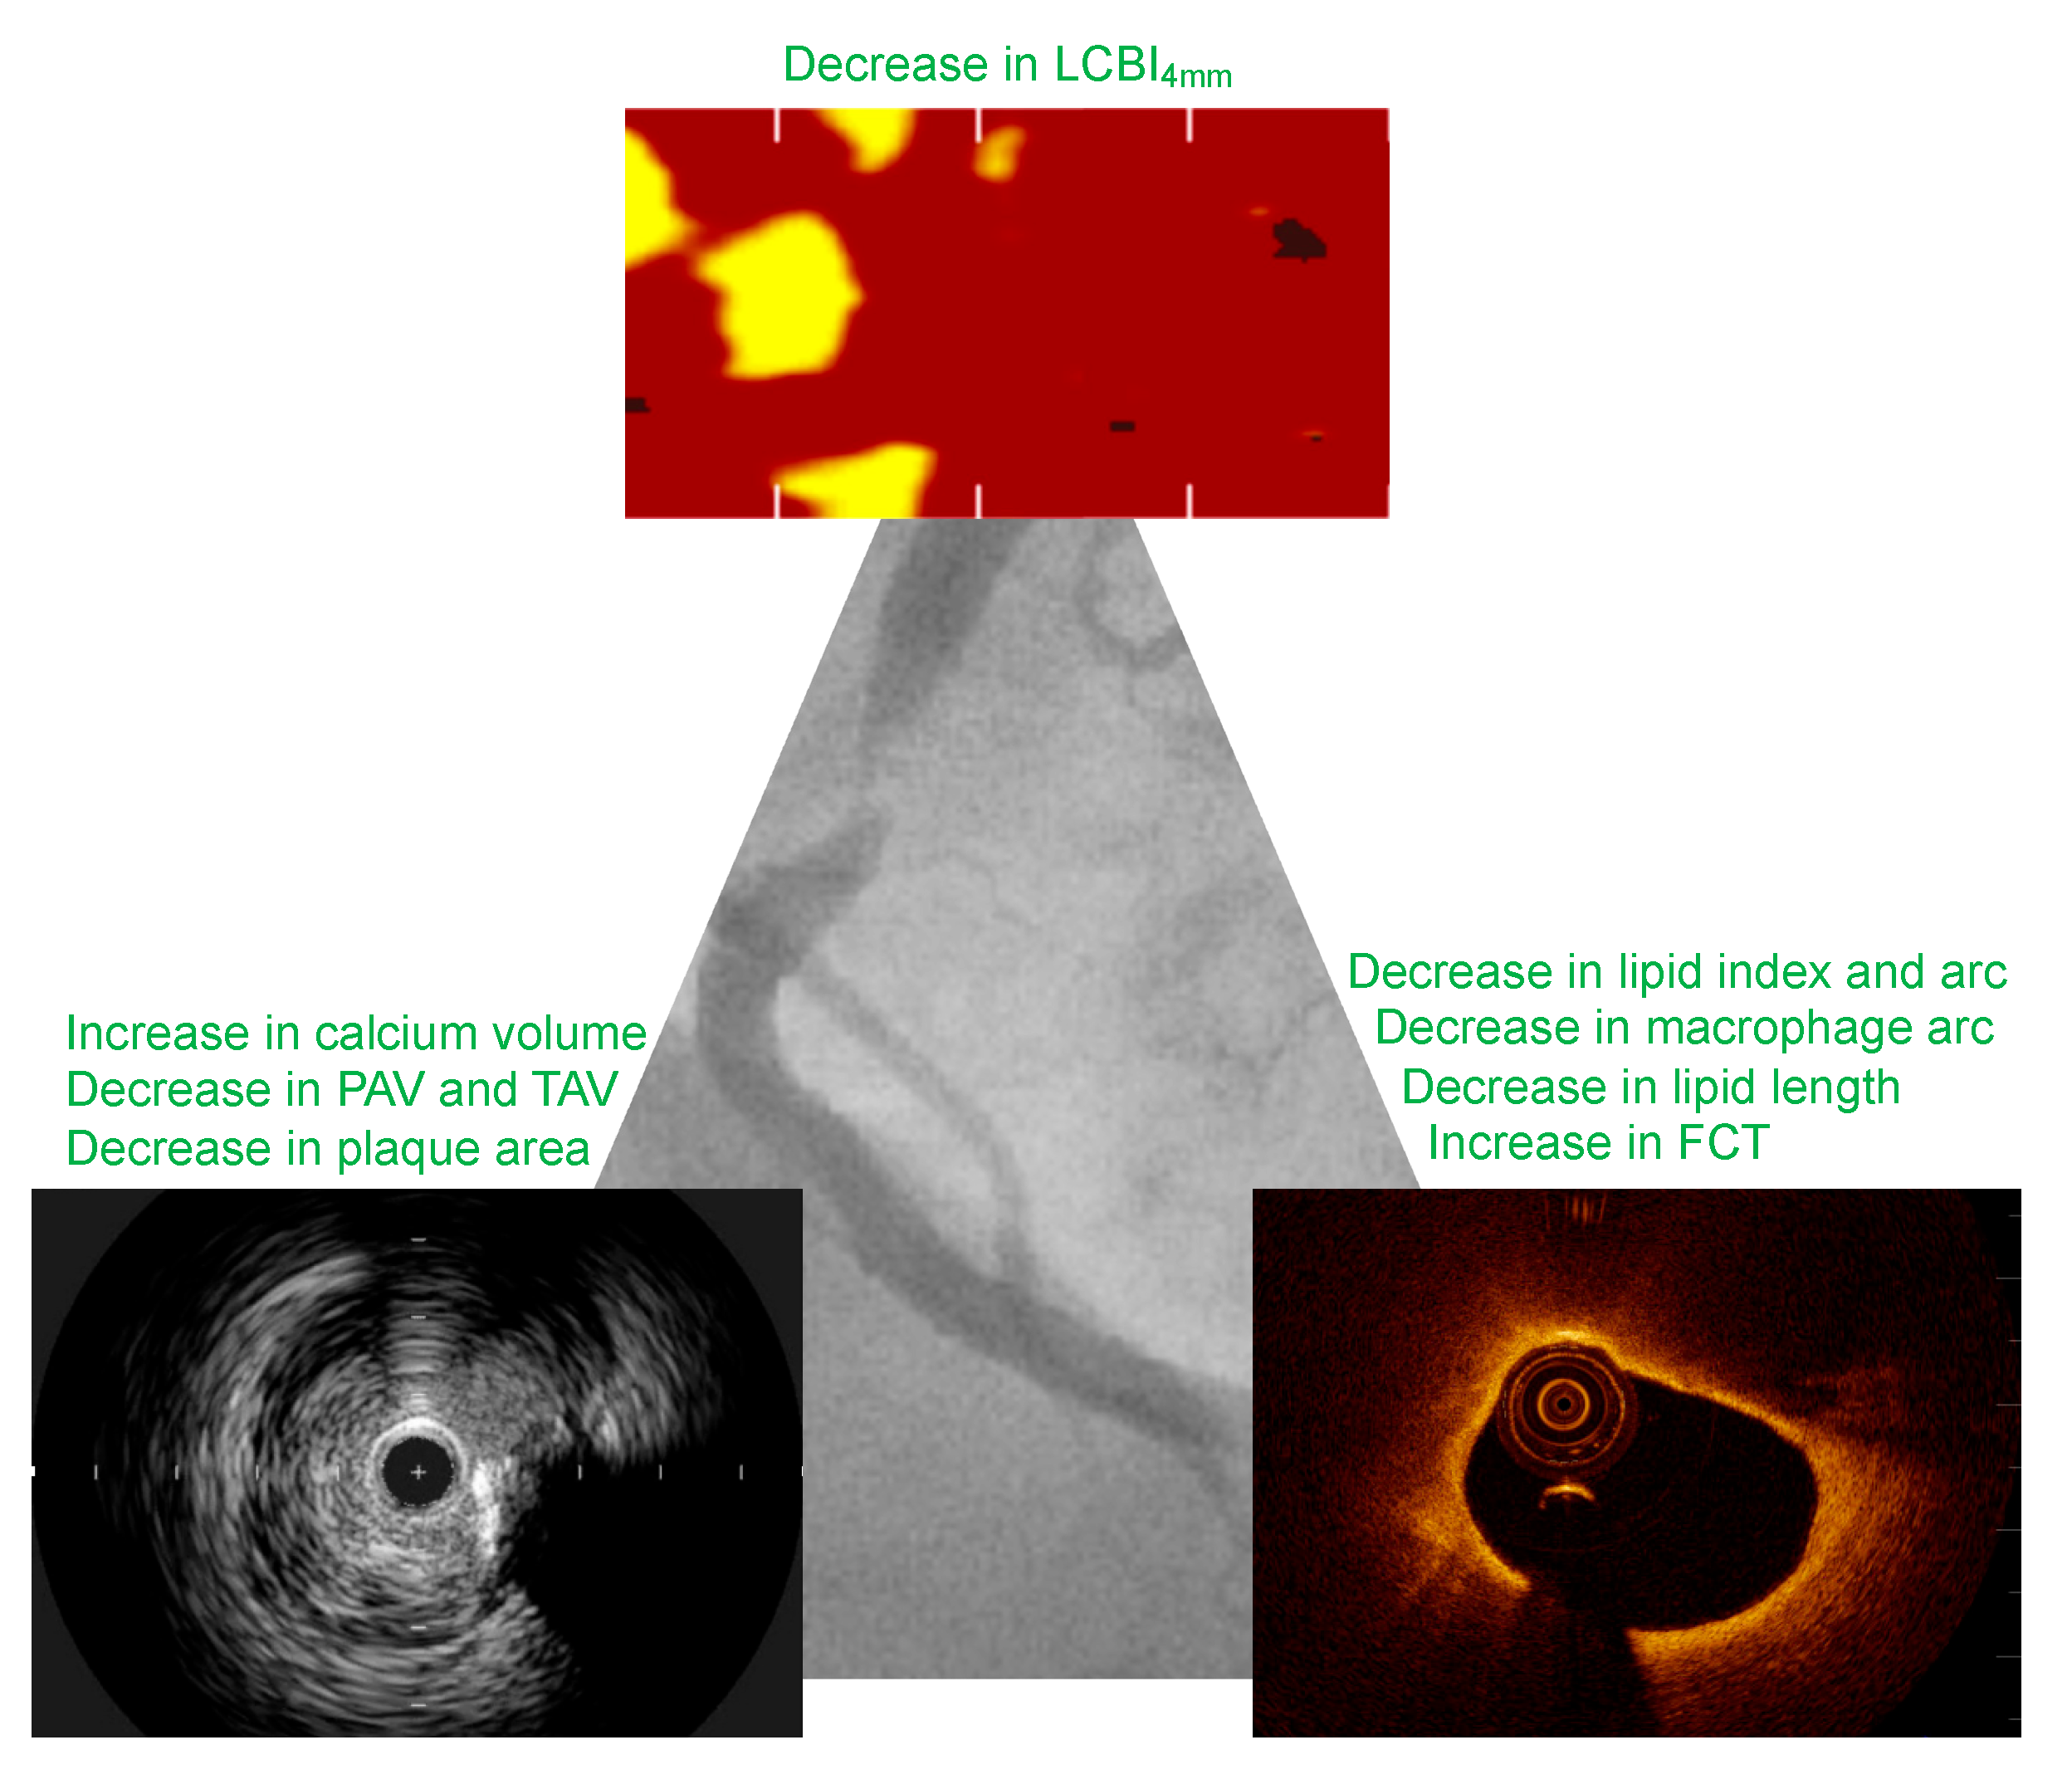

| Kini et al. [53] YELLOW 2013 | 87 patients with SA | Intensive statin therapy (40 mg rosuvastatin) vs. standard of care | 7 weeks | Median change in LCBI4 mm: −24.4 vs. 5.4% (p = 0.02) |

| Komukai et al. [49] EASY-FIT 2014 | 70 patients with UA | 20 mg vs. 5 mg atorvastatin | 12 months | Median change in FCT: 69 vs. 17% (p < 0.001) Median change in lipid arc: −27% vs. −8% (p < 0.001) Decrease in macrophage grade: −38 vs. −24% (p < 0.001) Median lipid length change: −0.6 vs. −0.4 mm (p = NS) |

| Raber et al. [51] IBIS-4 2019 | 103 patients with STEMI | Rosuvastatin 40 mg | 13 months | Values compared to baseline Mean minimum cap thickness change: 21.41 um (p = 0.008) Mean cap thickness change: 69.26 um (p < 0.001) Mean macrophage lines arc change: −3.22 (p < 0.001) Mean lipid arc change: −12.49 (p = 0.013) |

| Kuroda et al. [52] 2019 | 48 patients with SA and ACS | Rosuvastatin 10 mg + 1800 mg EPA vs. rosuvastatin 2.5 mg | 1 year | Median change in lipid length: −0.2 vs. 0.8 mm (p < 0.05) Median change in lipid arc: −2 vs. 19 (p < 0.05) Median change in lipid index: −45 vs. 217 (p < 0.05) Median change in macrophage grade: −16 vs. 18 (p < 0.05) |

| Raber et al. [54] PACMAN-AMI 2022 | 300 patients with ACS | 150 mg alirocumab (bi-weekly) vs. placebo | 52 weeks | Median PAV change: −2.13 vs. −0.92% (p < 0.001) Median TAV change: −26.12 vs. −14.97 mm3 (p < 0.001) Median LCBI change: −29.3 vs. −12.38 (p = 0.004) Mean FCT change: 90.95 vs. 62.36 um (p = 0.03) Mean angular extension of macrophages change: −25.98 vs. –15.95 (p < 0.001) |

| Nicholls et al. [55] 2022 | 161 patients with NSTEMI (79 patients with IVUS analysis) | Evelocumab 420 mg (monthly) vs. placebo | 52 weeks | Median minimum FCT change: 42.7 vs. 21.5 um (p = 0.015) Median maximum lipid arc change: −57.5 vs. −31.4 (p = 0.04) Median lipid length change: −5.8 vs. −3.3 mm (p = 0.02) Mean PAV change: −2.29 vs. −0.61 (p = 0.009) Mean TAV change: −19.0 vs. −8.9 mm3 (p = 0.04) |